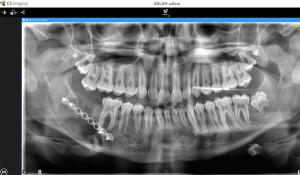

Dr. Farzin’s team designed a meticulous treatment plan that involved removing the tumor and impacted wisdom tooth, repositioning the nerve, and using a bone plate to reconstruct the jaw. Every step required extreme precision to avoid nerve damage and ensure Salem could regain full jaw functionality.

“The three-hour surgery was performed under general anaesthesia,” Dr. Farzin explained. “We carefully removed the tumour and wisdom tooth, repositioned the nerve, and inserted a bone plate to stabilize and reconstruct the jaw.”

The surgery was a success, significantly reducing Salem’s pain and swelling and preventing future complications. Salem’s immediate post-operative recovery brought much-needed relief to his family.